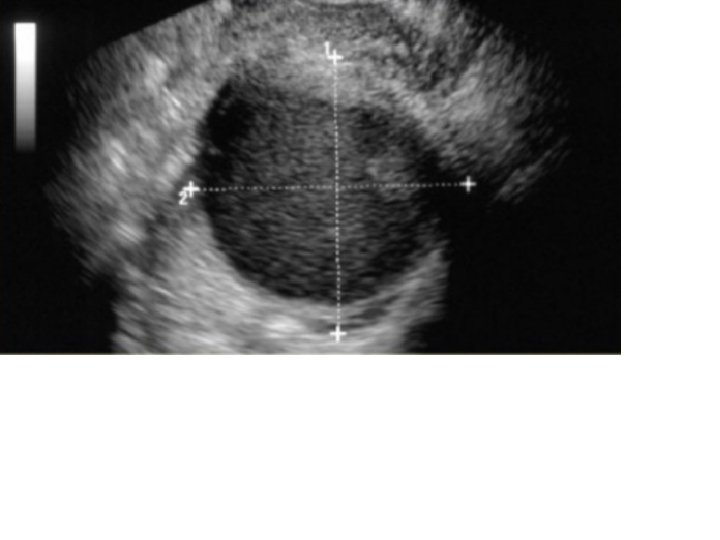

Endométrio normal no menacme, na fase ovulatória; aspecto trilaminar Paciente 60 anos evolui com sangramento pós menopausa →USG transvaginal Atrofia endometrial: principal causa de sangramento na pós menopausa, seguindo de pólipo endometrial e neoplasia maligna. Atrofia endometrial

USG: Útero pequeno, na menopausa; Endométrio espessado, heterogêneo, com áreas císticas → Biópsia + histeroscopia